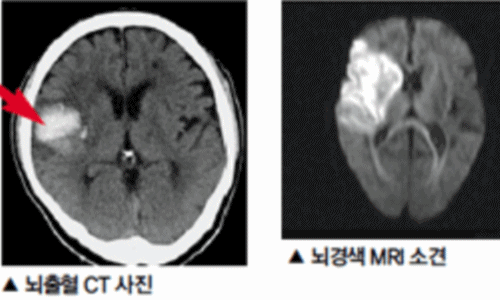

신체가 건강해도 뇌에 문제가 생기게 되면 신체 기능을 제대로 할 수가 없게 됩니다. 뇌 손상으로 제한된 신체 기능은 치료를 마친 후에도 회복이 제대로 되지 않거나 장애로 남는 경우가 많은데 뇌조직이 괴사되며 발생하게 되는 뇌경색이 대표적입니다. 과거에는 뇌출혈 환자가 많았지만 현재는 전체 뇌졸중 환자의 약 60~70%가 뇌경색 환자인 만큼 뇌졸중에서도 뇌경색이 차지하는 비중이 크다고 합니다.

건강보험심사평가원 자료에 따르면 뇌출혈로 병원을 찾은 환자보다 뇌경색으로 내원한 환자가 5배 이상 많았다고 하는데요 뇌경색은 뇌로 통하는 혈관이 막히면서 뇌 조직이 점차 괴사하게 되는 질환으로 날씨가 추워지는 겨울철에 특히 발생 가능성이 높은데요 혈관이 수축 하게 되면서 혈압 상승으로 이어지면서 뇌혈관 질환이 발생하게 되기 때문입니다.

뇌졸중에서도 혈관이 막히는 뇌경색이야말로 촌각을 다투는 응급질환이라고 볼 수 있습니다. 뇌혈관이 막히면서 점차 뇌세포가 괴사하기 때문에, 증상 발현 3시간 안에 혈전용해제를 투여하고 시술에 들어가야 심각한 상황을 면할 수 있습니다. 뇌경색 치료방법에 있어 가장 중요한 것은 혈전을 녹이는 혈전용해제를 정맥 투여함으로써 막힌 혈관을 뚫어주는 것입니다. 하지만 혈전용해제의 경우도 출혈 가능성이 있는 환자에게는 투여할 수 없으며, 또한 혈소판 수치가 낮아서 지혈이 되지 않는 경우에는 제외된다고 합니다.